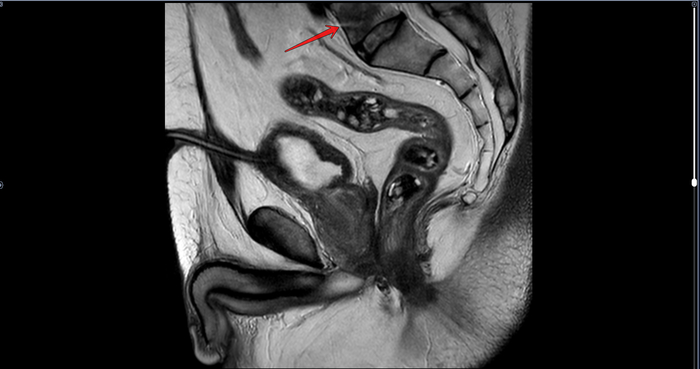

Преимущественно в периферической зоне предстательной железы, определяются участки, размерами 21х11мм,28х8мм, с 3 до 6 часов, с 6 до 11 часов условного циферблата гиперинтенсивного МР сигнала на DWI B1000,гипоинтенсивного сигнала на ИКД карте-соответствуют истинному ограничению диффузии. С быстрым накоплением контраста в раннюю артериальную фазу контрастирования, с последующим вымыванием контраста с позднюю артериальную фазу. В теле L5 позвонка -участок гипоинтенсивного сигнала на Т2 с не четкими, не ровными контурами,d 2.9см. Заключение: МР картина рака предстательной железы, V класс по PIRADS v.2.1. Участок в теле L5 позвонка наиболее соответствует mts. Состояние после троакарной цистостомии, биорхэктомии.